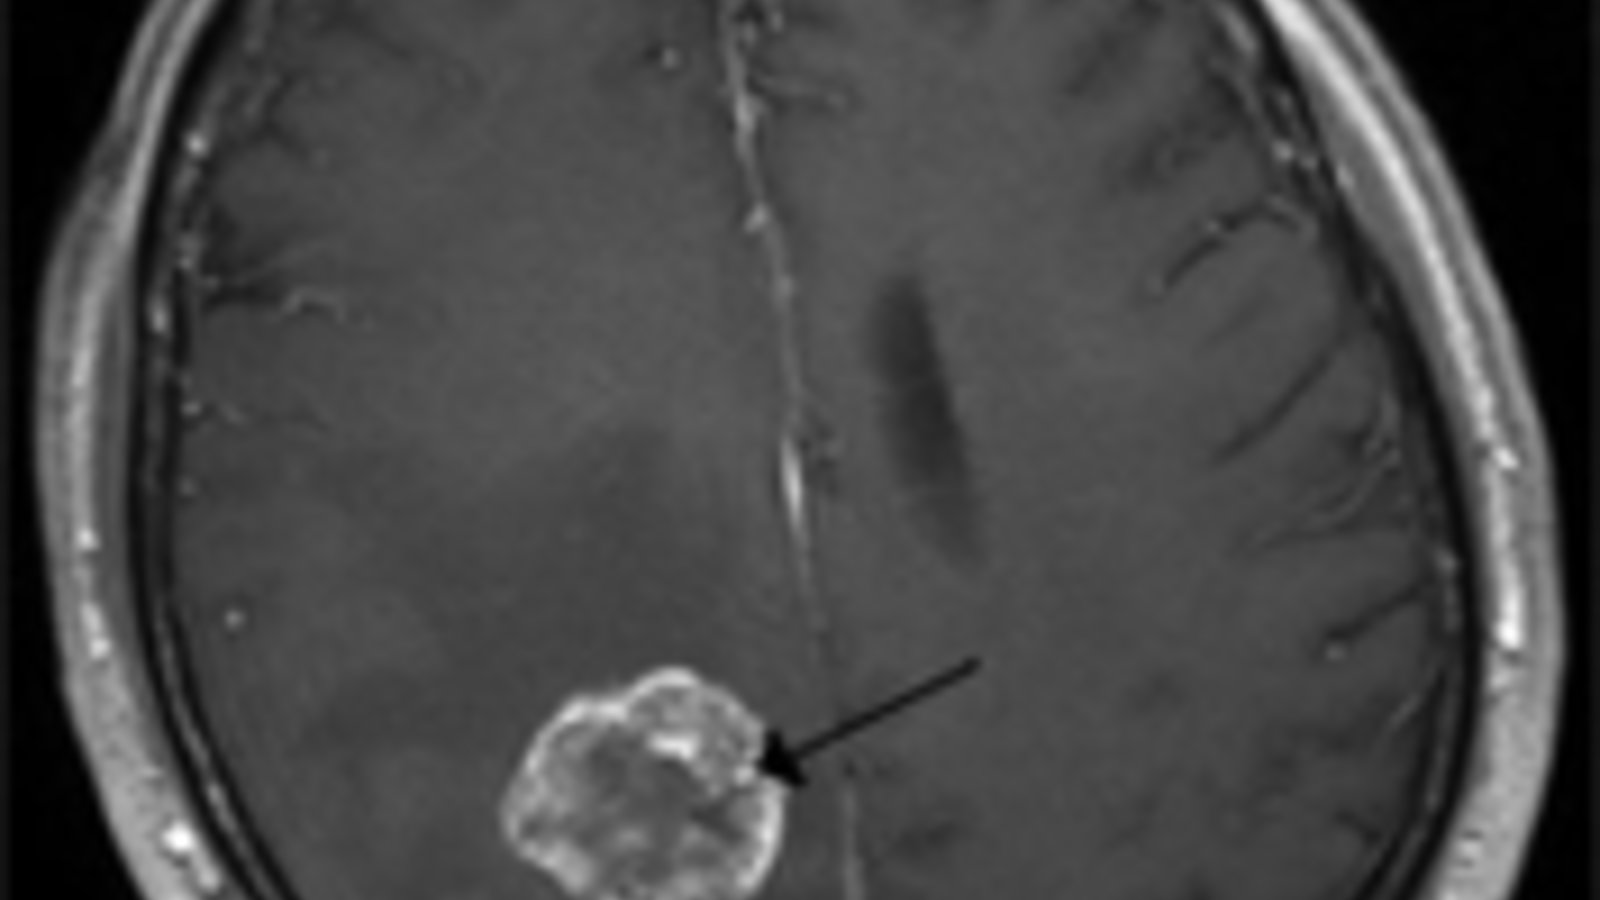

Que sait-on maintenant de l’origine des tumeurs cérébrales ? D’abord qu’elles peuvent se former à partir soit d'une cellule du cerveau lui-même ou d'une cellule métastasique exportée d'un cancer situé dans une autre partie du corps. Quand les cancers naissent dans le cerveau, ce sont le plus souvent des cellules gliales qui sont à leur origine. On appelle donc ces tumeurs « gliomes » et elles représentent 50 % à 60 % de toutes les tumeurs cérébrales (malignes et bénignes) détectées chez les enfants et les adultes). Le glioblastome en est la forme la plus commune et il faut le traiter immédiatement car il s’étend rapidement. Son incidence est environ de 5 cas pour 100 000 habitants. Le pic de fréquence se situe entre 50 et 60 ans. Ces tumeurs sont la troisième cause de mortalité chez le jeune adulte. Etc, etc, etc…

Tumeur du cerveau

Brain tumor